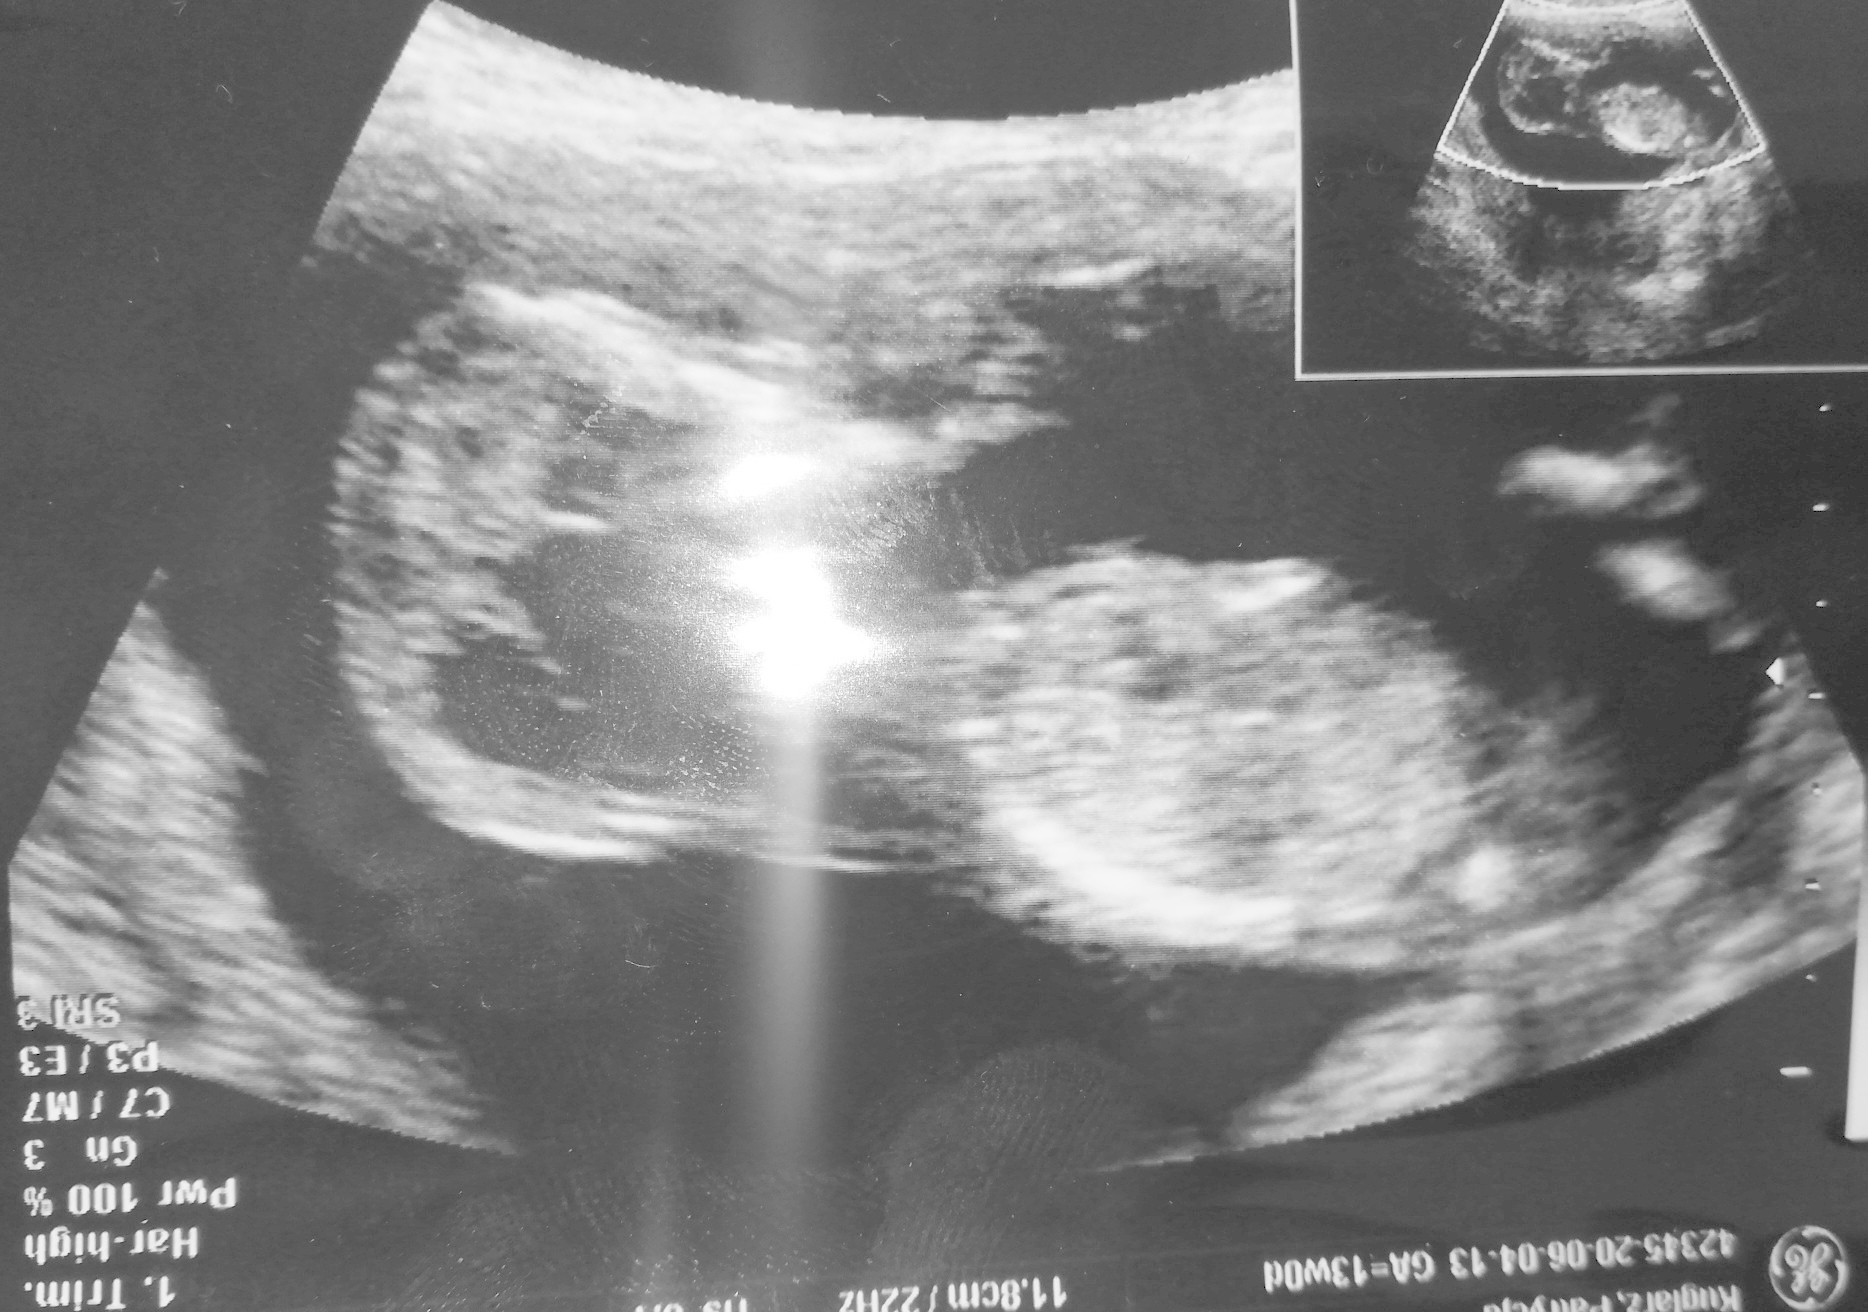

A na tym zdjęciu co dziś wstawiłam nie widzisz widełek? Na tym wczorajszym na grupie ramzi i nub, dziewczyny napisały że nie widać wyrostka. A na tym myślę, że coś widać 😁

Zobacz tam na tym końcu? Czy mi już znowu się coś wydaje 😂

Załączniki

• IMG_20200604_213917.jpg

IMG_20200604_213917.jpg

396,1 KB · Wyświetleń: 82

• IMG_20200604_213937.jpg

IMG_20200604_213937.jpg

47,2 KB · Wyświetleń: 87

Ja na tym nie widzę tak bardzo wyślij to wczorajsze to Ci zaznaczę gdzie mi się widzialo:D

Ja wiem o które miejsce wczoraj Ci chodziło, bo sama tak myślalam. Ale to było za nisko, tak jakby przedłużenie kręgosłupa 😅 tutaj też mam wrażenie, że w sumie to może nie być nub bo też trochę nisko. Wyżej niż to wczoraj, ale nisko

Hej. Ja tylko na chwilke. Wiem ze niektore osoby pamietaly ze mam prenatalne i pewnie czekają na wieści. Duma mnie rozpiera i tryskam dzis pozytywna energia po badaniu wiec chce to pokazac calemu swiatu [emoji4] płeć nieznana bo sie nie pokazaliśmy [emoji28] straszny wiercioch ogólnie. Ryzyko takie jak na zdj [emoji4] 2 w tabelce to skorygowane. Cale 6.6 cm szczescia. Także u nas dobrze gdyby coś. Buziaki [emoji173]

Dziewczyny u nas wszystko okej [emoji176] wszystkiej parametry dobre, serduszko bije 163/min. Dzidzia ma 6,72cm, ryzyko wad niskie. No i jestem szczęśliwa, bo najprawdopodobniej będzie córcia [emoji7] ewidentnie było widać widełki [emoji179]